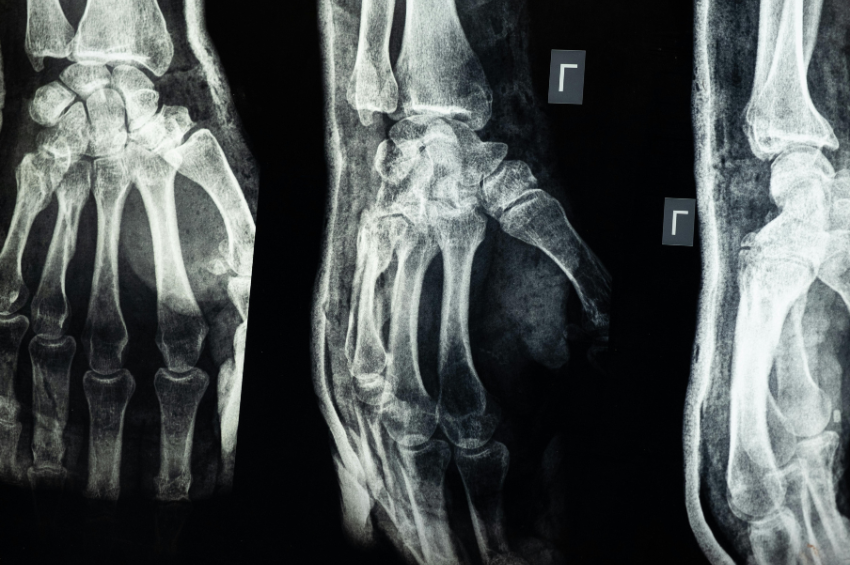

Crean un vidrio impreso en 3D que podría reemplazar huesos humanos

De acuerdo con medios oficiales, se trata de un vidrio bioactivo imprimible en 3D que podría servir como una especie de “andamio”. Pero este no solo podrá reemplazar un hueso que ya no está, sino que tendrá la capacidad de estimular su crecimiento de forma natural.

Como hemos mencionado al principio, se trata de un vidrio imprimible en 3D que podría reemplazar a un hueso faltante. Asimismo, sería capaz de estimular su crecimiento naturalmente.

Esto demuestra una efectividad superior, tanto a la del vidrio común, como a la de los injertos óseos comerciales que se derivan de animales. Los implantes óseos también han sido fabricados con metal o con huesos donados.

Pero, con la llegada de este nuevo material, se abren las puertas hacia mejores tratamientos, así como más investigaciones que realzan los beneficios de la impresión tridimensional. Lo que ayudará a crear estructuras personalizadas para cada paciente.